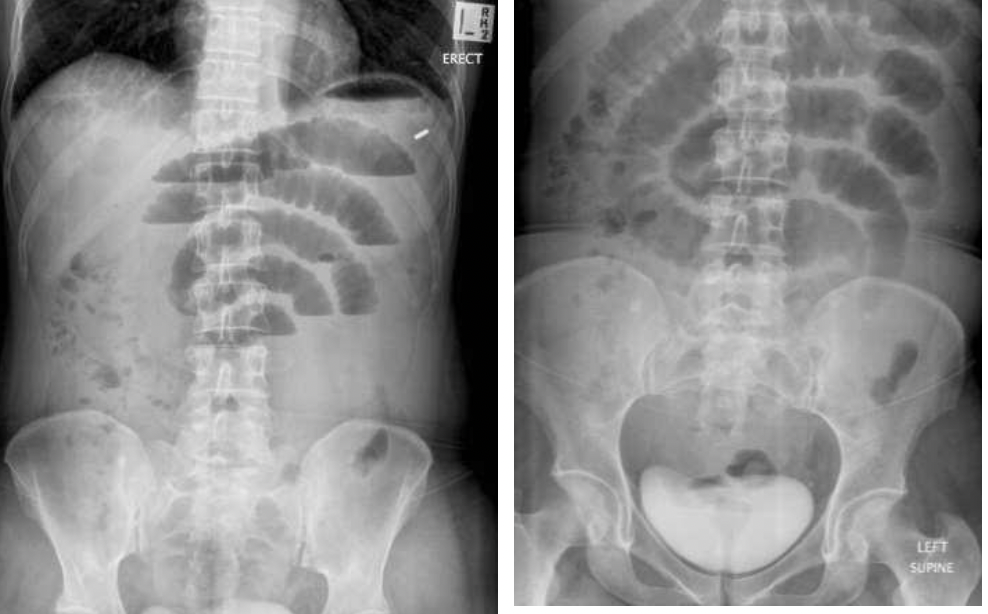

משמאל- ניתן לראות פלס אוויר- נוזל בריבה. כאשר לולאות המעי הדק רחבות מעל ל3 מ״מ זה מעיד על חסימה.

מימין- הצילום נעשה בשכיבה (שייך לאותו חולה), רואים את האוויר, אי אפשר לראות פלסים כי זה בשכיבה.